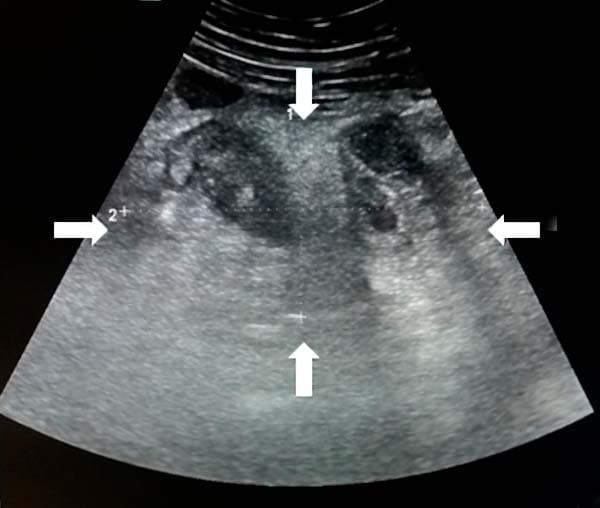

Характерные признаки острой кишечной непроходимости при ультразвуковом исследовании: петли тонкой кишки заполнены жидкостью, расширены до 25–30 мм и более; перистальтика маятникообразная или отсутствует; визуализируются циркулярные складки (в этом отличие тонкой кишки от толстой); может определяться свободная жидкость межпетельно (не всегда) (см. рис. 19).

Пример описания: «В гипогастрии визуализируются расширенные до 30–40 мм петли тонкого кишечника, наполненные жидкостью, с вялой маятникообразной перистальтикой; определяется свободная жидкость межпетельно» (см. рис. 20).

Рисунок 20. Острая кишечная непроходимость.